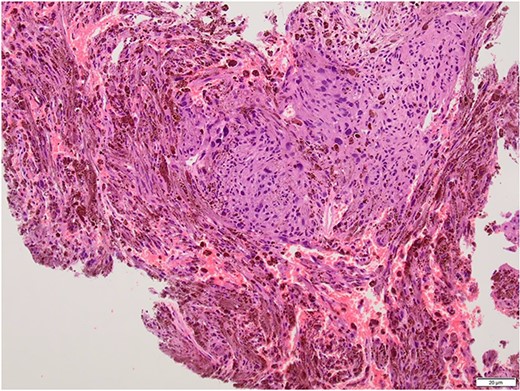

Intralesional debulking of the lesion was carried out with no complications in June 2021. Histopathology results confirmed a malignant melanotic peripheral nerve sheath tumour (schwannoma) (Fig. 5). She underwent a further procedure to attempt a complete excision of the lesion. Patient consent for publication was obtained.

Histopathology slide with the tumour being composed of fascicles and pleomorphic cells obscured by the melanin pigment.